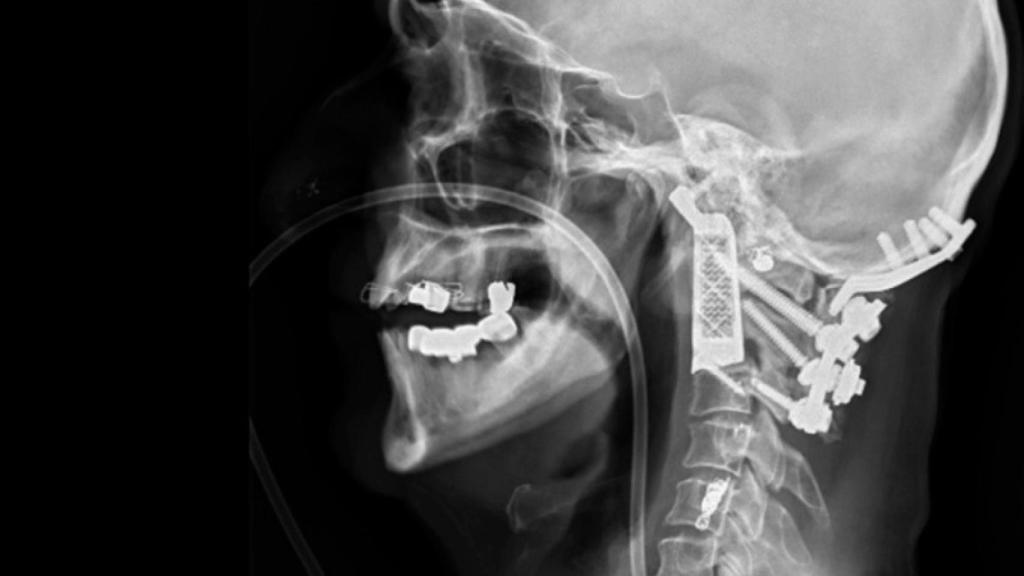

Eso es lo que ha ocurrido en Sídney, Australia, donde el neurocirujano Ralph Mobbs ha utilizado la impresión 3D para eliminar un tumor en la base del cráneo de un paciente de 60 años y sustituir las dos vértebras a las que había afectado, de otro modo el avance del cáncer le habría dejado sin movilidad.

No es la primera vez que se reconstruyen vértebras utilizando hueso del paciente, pero Mobbs decidió innovar y probar con la impresión 3D para lograr un mejor resultado.

Trabajó en conjunto con la empresa Anatomics, que no sólo se encargaron de imprimir en titanio el implante de las vértebras, sino que también crearon por impresión 3D varios modelos de la anatomía de la zona exactamente como la del paciente. ¿Para qué? de esta forma el neurocirujano podría ensayar la operación.

Pese a las facilidades, la operación duró más de 15 horas pero todo ha salido bien y el paciente ya se está recuperando. Este neurocirujano, al igual que otros profesionales del sector, tiene grandes expectativas en la impresión 3D, principalmente cuando se consiga mejorar la impresión de tejidos orgánicos, de modo que no se utilicen materiales como titanio, sino imprimir órganos utilizando las propias células del paciente.